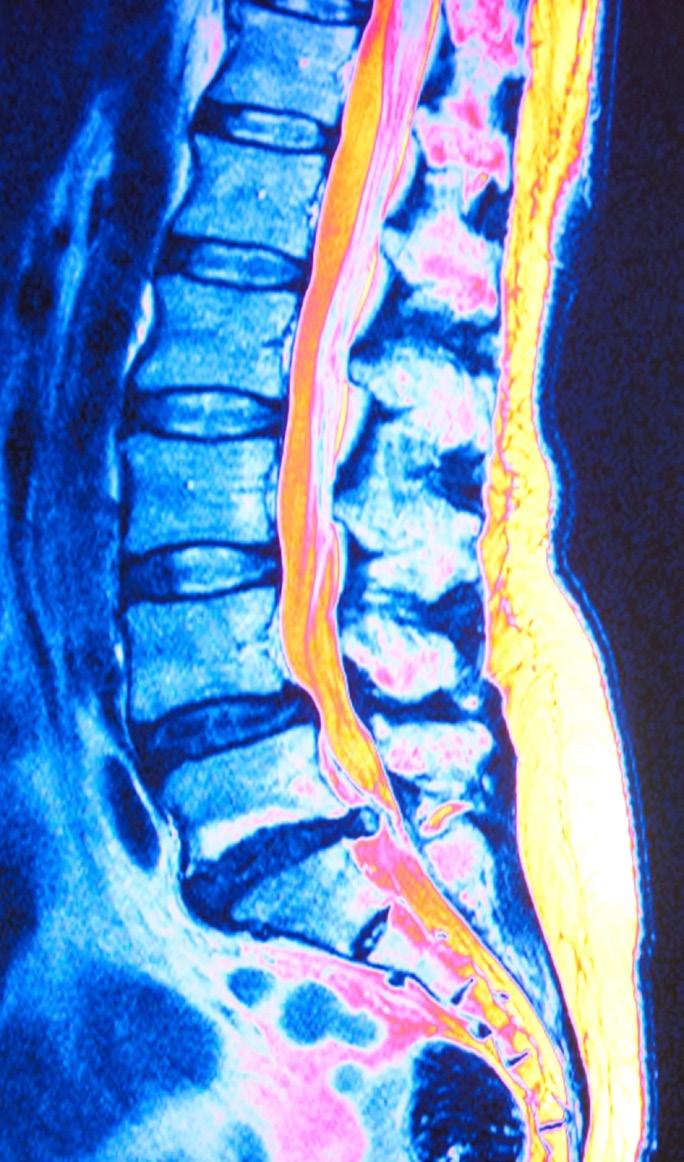

UNDERSTANDING SPINAL STENOSIS and a Path to Relief through

Minimally Invasive Lumbar Decompression (MILD)

Spinal stenosis is a debilitating condition that affects many individuals, particularly as we age. Spinal stenosis involves the narrowing of spaces within the spine, causing compression onto the spinal cord and nerves coming from the spinal cord that go to muscles throughout your body. This narrowing can occur in most parts of the spine but is most common in the lower back (lumbar spine), where it can significantly impact a person’s function and quality of life.

The Anatomy of Spinal Stenosis

The spine consists of vertebrae (made of bone) stacked upon one another.

These vertebrae have a hollow space that holds and protects the spinal cord and nerve roots, called the spinal canal. In spinal stenosis, the open spaces between the vertebrae within the spine narrow, placing pressure on the spinal cord and nerves.

Diagnosing Spinal Stenosis

The result of spinal stenosis is often pain, numbness, or weakness, particularly in the legs. Pain is often described as a burning pain radiating to the buttocks and legs that worsens with extended periods of standing or walking. One common symptom that can help your pain provider diagnose spinal stenosis

is called the “shopping cart sign.” Have you experienced leg pain and weakness while grocery shopping only to find relief when leaning over the cart? This is often reported by patients with spinal stenosis. The reason patients get relief when they lean over the cart is because it opens or widens the spinal space between vertebrae and relieves the pressure on the nerves.

Functional Impact: Navigating Life with Spinal Stenosis

Patients with spinal stenosis may find their daily lives significantly altered. The pain and discomfort associated with the condition can limit one’s ability to

stand or walk for extended periods, affecting everything from daily errands to enjoying recreational activities. For those accustomed to an active lifestyle, the impact can be particularly challenging, diminishing not only physical function, but also the overall quality of life.

A Ray of Hope: Minimally Invasive Lumbar Decompression (MILD)

Traditionally, surgical interventions have been considered for spinal stenosis; however, the field of interventional pain management has witnessed significant advancements, bringing forth less invasive alternatives. One such innovation is Minimally Invasive Lumbar Decompression (MILD). This outpatient procedure is designed to address the root cause of spinal stenosis without the need for major surgery.

How MILD Works: Precision and Effectiveness

MILD specifically targets the areas of the spine contributing to stenosis. Under x-ray guidance, a specialized tool is used to remove small pieces

of bone and excess ligament tissue, which mechanically enlarges the spinal canal and relieves the pressure on nerves. The beauty of MILD lies in its minimally invasive nature, requiring only a small incision and resulting in less postoperative discomfort and a quicker recovery. In many successful cases, patients are able to stand upright without pain for the first time in years within minutes following the procedure.

Paving the Way for a More Active Tomorrow

Understanding spinal stenosis empowers patients to explore innovative solutions with their care team. MILD is not just a procedure; it represents a step toward a more active life not controlled by pain. If you or a loved one is grappling with the challenges of what you suspect could be spinal stenosis, know that advancements in pain management treatments offer new avenues for relief. Let’s embark on a journey to reclaim the joys of movement and rediscover a life unhindered by pain.